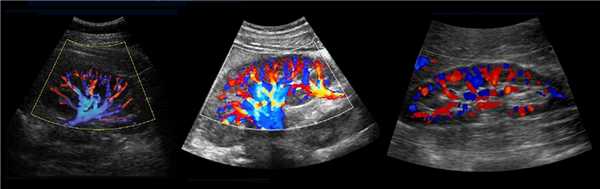

Рисунок. В воротах почки главная почечная артерия делится на пять сегментарных: задняя, верхушечная, верхняя, средняя и нижняя. Сегментарные артерии разделяются на междолевые артерии, которые располагаются между пирамидками почки. Междолевые артерии продолжаются в дугообразные → междольковые → приносящие артериолы клубочков → капиллярные клубочки. Кровь от клубочка отходит по выносящей артериоле в междольковые вены. Междольковые вены продолжаются в дугообразные → междолевые → сегментарные → главную почечную вену → нижнюю полую вену.

Рисунок. В норме при ЦДК сосуды почек прослеживаются до капсулы (1, 2, 3). Главная почечная артерия входит через ворота почки, добавочные артерии из аорты или подвздошной артерии могут подходить у полюсов (2).

Доплер сосудов почки в норме

Почечную артерию следует оценивать в семи точках: при выходе из аорты, в проксимальном, среднем и дистальном сегментах, а так же верхушечную, среднюю и нижнюю сегментарные артерии. Оцениваем пиковую систолическую (PSV) и конечно-диастолическую (EDV) скорости кровотока, индекс резистивности (RI), время ускорения (АТ), индекс ускорения (PSV/АТ). Подробнее смотри Доплер сосудов.

Нормальный спектр почечных артерий имеет выраженный систолический пик с антеградным диастолическим потоком на протяжении всего сердечного цикла. У взрослых в норме на главной почечной артерии PSV 100±20 см/сек, EDV — 25-50 см/сек, у детей раннего возраста PSV 40-90 см/сек. В сегментарных артериях PSV падает до 30 см/сек, в междолевых до 25 см/сек, в дуговых до 15 см/сек и междольковых до 10 см/сек. RI в воротах почки